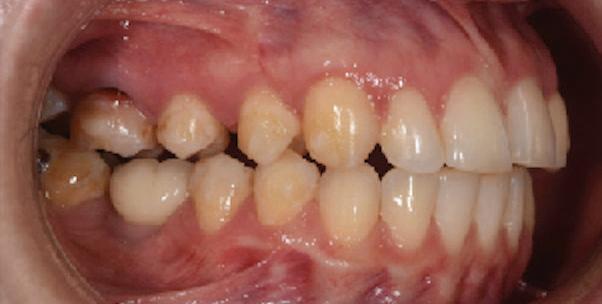

20 Dental Tribune Bulgarian Edition / октомври 2022 г. П ациентите със завършен растеж и скелетни проблеми обикновено представляват предизвикателство за ортодонт ската практика. Необходимостта от изваждане на зъби в комбинация с особеностите на възрастовата ортодонтия изисква особено внима ние. Фокусът върху критично важното значение на позицията на долните резци във връзка с дългосроч ната стабилност и постигането на оптимални оклузални взаимоотношения при затварянето на екстракционните пространства лесно може да излезе извън контрол. Когато към тези чисто кли нични проблеми се добави и стресът от натоваре ната практика, предизвикателството става още по-голямо. Всички тези фактори налагат използ ването на доказан подход с ясни и последовател ни стъпки, в което се разкрива силата на дисциплината „Алекзандър“ – предвидим протокол през целия процес на елиминиране на ротациите, ниве лиране на дъгите, затваряне на екстракционните пространства и финализиране на случая. Именно такъв е и случаят, който презентираме –екстракционен, скелетен клас 3 при възрастен па циент, лекуван по системата „Алекзандър“. ПРЕДВИДИМИ РЕЗУЛТАТИ ПРИ ПАЦИЕНТИ СЪС ЗАВЪРШЕН РАСТЕЖ И СКЕЛЕТЕН КЛАС 3, ИЗПОЛЗВАЙКИ ЕКСТРАКЦИОННО ЛЕЧЕНИЕ ПО ДИСЦИПЛИНАТА „АЛЕКЗАНДЪР“ Д-р Радой Димитров, България Преди започване на лечение клиничен случай | ортодонтия Фиг. 1а–1e Преди започване на лечение. Пациентът пристига в практиката с основното оплакване от невъзмож ност за нормално дъвчене. Снета е цялата необходима диагностична ин формация. Фиг. 1f–1h Снимки в профил и анфас. Фиг. 1i–1k Панорамна снимка, телерентгенография и анализ на телерент генография. Фиг. 1а Фиг. 1d Фиг. 1f Фиг. 1g Фиг. 1h Фиг. 1e Фиг. 1b Фиг. 1c Фиг. 1i Фиг. 1j Фиг. 1k

closed.

21Dental Tribune Bulgarian Edition / октомври 2022 г. ДИАГНОСТИЧНИ РЕЗУЛТАТИ: 1. Възраст на пациента: 21 години 2. Скелетен клас III (ANB 0) 3. Зъбен клас 3 4. Ръбцова захапка във фронта, кръстосана в дисталните участъци 5. Тясна горна челюст 6. Overjet – 0 мм, Overbite – 0 мм 7. Несъответствие на горната с долната средна линия 8. Единични контакти в ЦО 9. Хиподивергентен тип на растеж SN/MP – 33.5 10. Неравен гингивален контур 11. Неравна линия на усмивката 12. Тенденция за рецесии в долен фронт ПРЕПОРЪЧИТЕЛНО ЛЕЧЕНИЕ: Пълно ортодонтско лечение с метални брекети „Алекзандър“ Корекция на клас 3 захапката в областта на кучешките зъби с екстракция на първите пре молари в долна челюст Корекция на кръстосаната захапка в дистални участъци Коригиране на ръбцовата захапка във фронта Подобряване на ОJ и OB на пациента Стрипинг в долен фронт Подреждане на зъбите в горната и долната челюст Професионално хигиенизиране и профилактични дентални прегледи са препоръчителни на всеки 6 месеца. 1-ви месец След 1 месец са залепени брекети в горната челюст – поставена е еластична дъга. 016 NiTi. В долната челюст са елиминирани ротациите, поставена е стоманена дъга. 016SS, закалена с ток, и еластична верижка за затваряне на пространствата. 3-ти месец В долната челюст е поставена трета дъга – 17 x 25 NiTi с къси лигатури и верижка

В горната челюст се затварят пространствата с дъга .016SS и верижка. 5-и месец На 5-ия месец след залепяне на брекетите в долната челюст е поставена стоманена дъга 16 x 22 SS с четвъртито сечение, омега луп и тай бек. В горната челюст е поставена дъга 17 x 25 NiTi. Поради липсата на стабилни оклузални контакти са поставени лингвални верижки в областта на моларите, за да се предотврати нежелана ротация на 7-ите зъби. 6-и месец На 6-ия месец от началото на лечението са екстрахирани долните първи премолари, поставена е дъга 16 x 22 SS със затваряща чупка teardrop. Чупката се активира всеки месец по 1 мм с чинч-бек. клиничен случай | ортодонтия СТЪПКИ НА ЛЕЧЕНИЕТО Начало на лечението Лечението започва с поставяне на апарат за бърза експанзия в горната челюст. През първия месец от лечението са направени 24 оборота на апарата за експанзия. Залепени са брекети в долната челюст, поставена е дъга 17x25 CuNiTi, като са предпи сани клас 3 ластици (1/4”,4 1/2 oz) по време на сън, за да се осигури контрол върху торка на долните резци. Фиг. 2а Фиг. 3a Фиг. 4a Фиг. 3b Фиг. 4b Фиг. 3c Фиг. 4c Фиг. 3d Фиг. 4d Фиг. 3e Фиг. 4e Фиг. 5a Фиг. 5b Фиг. 5c Фиг. 5d Фиг. 5e Фиг. 6a Фиг. 6b Фиг. 6c Фиг. 6d Фиг. 6e Фиг. 7a Фиг. 7b Фиг. 7c Фиг. 7d Фиг. 7e Фиг. 2b Фиг. 2c Фиг. 2d

Dental Tribune Bulgarian Edition / октомври 2022 г.22 клиничен случай | ортодонтия 14-и месец В горната и долната челюст са поставени последни стоманени дъга с омега луп и тай бек – 17 x 25 SS с четвъртито сечение. Назначени е ластик за средната линия в комбинация с клас 3 ластик (1/4”, 6 1/2 oz). Контролни рентгенографии 13-и месец Екстракционните пространства са затворени. Направена е контролна панорамна снимка за оценка позицията на корените. Взето е решение за презалепване на брекетите на 12, 22 и пръстените на 36 и 46. 21-ви месец Средната линия в горната и долната челюст съвпадат. Ластиците са спрени. Свалени са пръстените и брекетите в горната и долната челюст, зигзаг ластици не са използвани поради благоприятните оклузални взаимоотношения. Фиг. 11j Ортопантомография в края на лечението. Фиг. 11k Телерентгенография след края на лечението. Фиг. 11l Анализ на телерентгенографията след лечението. Фиг. 11m Последователност на дъгите в горната и долната челюст Фиг. 11n Суперимпозиция на PreOp и PostOp ортопантомографии. 10-и месец Затварянето на пространствата е предвидимо и контролирано, без да се отварят пространства в зъбната дъга. Фиг. 8a Фиг. 8b Фиг. 8c Фиг. 8d Фиг. 8e Фиг. 10a Фиг. 10b Фиг. 10c Фиг. 10d Фиг. 10e Фиг. 9a Фиг. 9b Фиг. 9c Фиг. 9d Фиг. 9e Фиг. 9f Фиг. 11a Фиг. 11f Фиг. 11j Фиг. 11l Фиг. 11m Фиг. 11n Фиг. 11k Фиг. 11g Фиг. 11h Фиг. 11i Фиг. 11b Фиг. 11c Фиг. 11d Фиг. 11e

Dental Tribune Bulgarian Edition / октомври 2022 г. 23клиничен случай | ортодонтия реклама Лечението е продължило 21 месеца. Проведено е домашно избелване с индивидуални шини. За автора: Д-р Радой Димитров завършва с отличие Факултета по дентална медицина към МУ–София през 2015 г. В продължение на 5 години работи в няколко водещи практики в София, като през 2019 г. заедно със своята съпру га д-р Траяна Димитрова основават собствена практика в гр. Гоце Делчев –Dimitrovi Dental Care. Посещава редица курсове за повишаване на квалификаци ята, но най-сериозен тласък в развитието на ортодонтската си практика получава след завършването на комплексната ортодонтска програма, воде на от д-р Иван Горялов, базирана на дисциплината „Алекзандър“ – система с повече от 50 години опит в целия свят. Д-р Димитров е член на Българския изследователски клуб „Алекзандър“. Взе ма участие като гост-лектор в симпозиума с международно участие The Power of the Alexander Discipline, който се проведе на 14–15.05.2022 г. С д-р Ди митров можете да свържете на тел. +359885 252 025. Заключение Представеният случай е ярък пример за възможностите и красо тата на дисциплината „Алекзандър“ – приложен е утвърден под ход с ясни правила и са постигнати очакваните цели. Резулта тът ще бъде дългосрочно стабилен, тъй като са спазени всички правила, които се отнасят към максимално комфортната пози ция на зъбите в края на лечението. Постигнати са красива усмив ка и стабилна оклузия. ПОСТИГНАТИ РЕЗУЛТАТИ ОТ ЛЕЧЕНИЕТО 1. Коригирана ръбцова захапка 2. Коригирана клас 3 захапка в областта на ку чешките зъби 3. Коригирана кръстосана захапка в дисталните участъци 4. Коригиран овърджет и овърбайт 5. Разширена е горната зъбна дъга 6. Подредени зъби в горната и долната челюст 7. Постигната е стабилна захапка с множество контакти в ЦО 8. Драматично е подобрена дъвкателната функ ция 9. Подобрена е линията на усмивката ДРУГИ ПРОВЕДЕНИ ДЕНТАЛНИ ПРОЦЕДУРИ 1. Домашно избелване на зъбите 2. Екстракция на мъдреците Фиг. 12a Фиг. 12b Фиг. 12c Фиг. 12eФиг. 12d Фиг. 12f Фиг. 12g Информация за дати, цени и отстъпки www.bracescourses.com 0889 22 55 01 Практически курсове лектор д-р Иван Горялов Дисциплината „Алекзандър“ ПЪТЯТ КЪМ СУПЕРУСМИВКИТЕ 100% връщане на цялата сума, ако не сте удовлетворени след преминаване на Ниво 1 Директно и индиректно залепяне на брекети Анализ, диагноза и план на лечение Лечение на клас 2 дълбока захапка Екстракционно лечение Лечение на клас 3 отворена захапка НИВО 5НИВО 1 НИВО 2 НИВО 3 НИВО 4